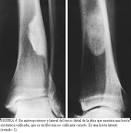

En radiografías, la lesión aparece en la metafísis de manera excéntrica y apariencia lítica. El curetaje es el tratamiento de elección para la mayoría de estos tumores. Es un tipo de tumor extremadamente raro y constituye menos del 1% de los tumores de hueso. El FCM se encuentra frecuentemente en la metafísis de la rodilla, tibia proximal, fibula proximal y fémur distal.

En radiografías, la lesión es excéntrica y de apariencia lítica con márgenes propiamente definidos en la metafísis de extremidades inferiores. Usualmente la lesión tiene un margen de hueso esclerótico y forma lobulada. Crestas y depresiones que aparecen en los márgenes confieren una apariencia trabeculada. Estudios de TAC ayudan a definir la integridad cortical y a confirmar que no haya mineralización de la matriz como en otros tumores de cartílago. El FCM, al igual que otros tumores de cartílago, presenta una señal atenuada en imágenes de RNM tipo T1 y señales aumentadas en imágenes de tipo T2. Estudios de RNM son particularmente útiles en la planificación preoperativa y determinación de estadíos. El diagnóstico diferencial radiológico incluye tumores de células gigantes, quiste óseo aneurismático (QOA), quiste óseo unicameral (QOU), condroblastoma y displasia fibrosa.